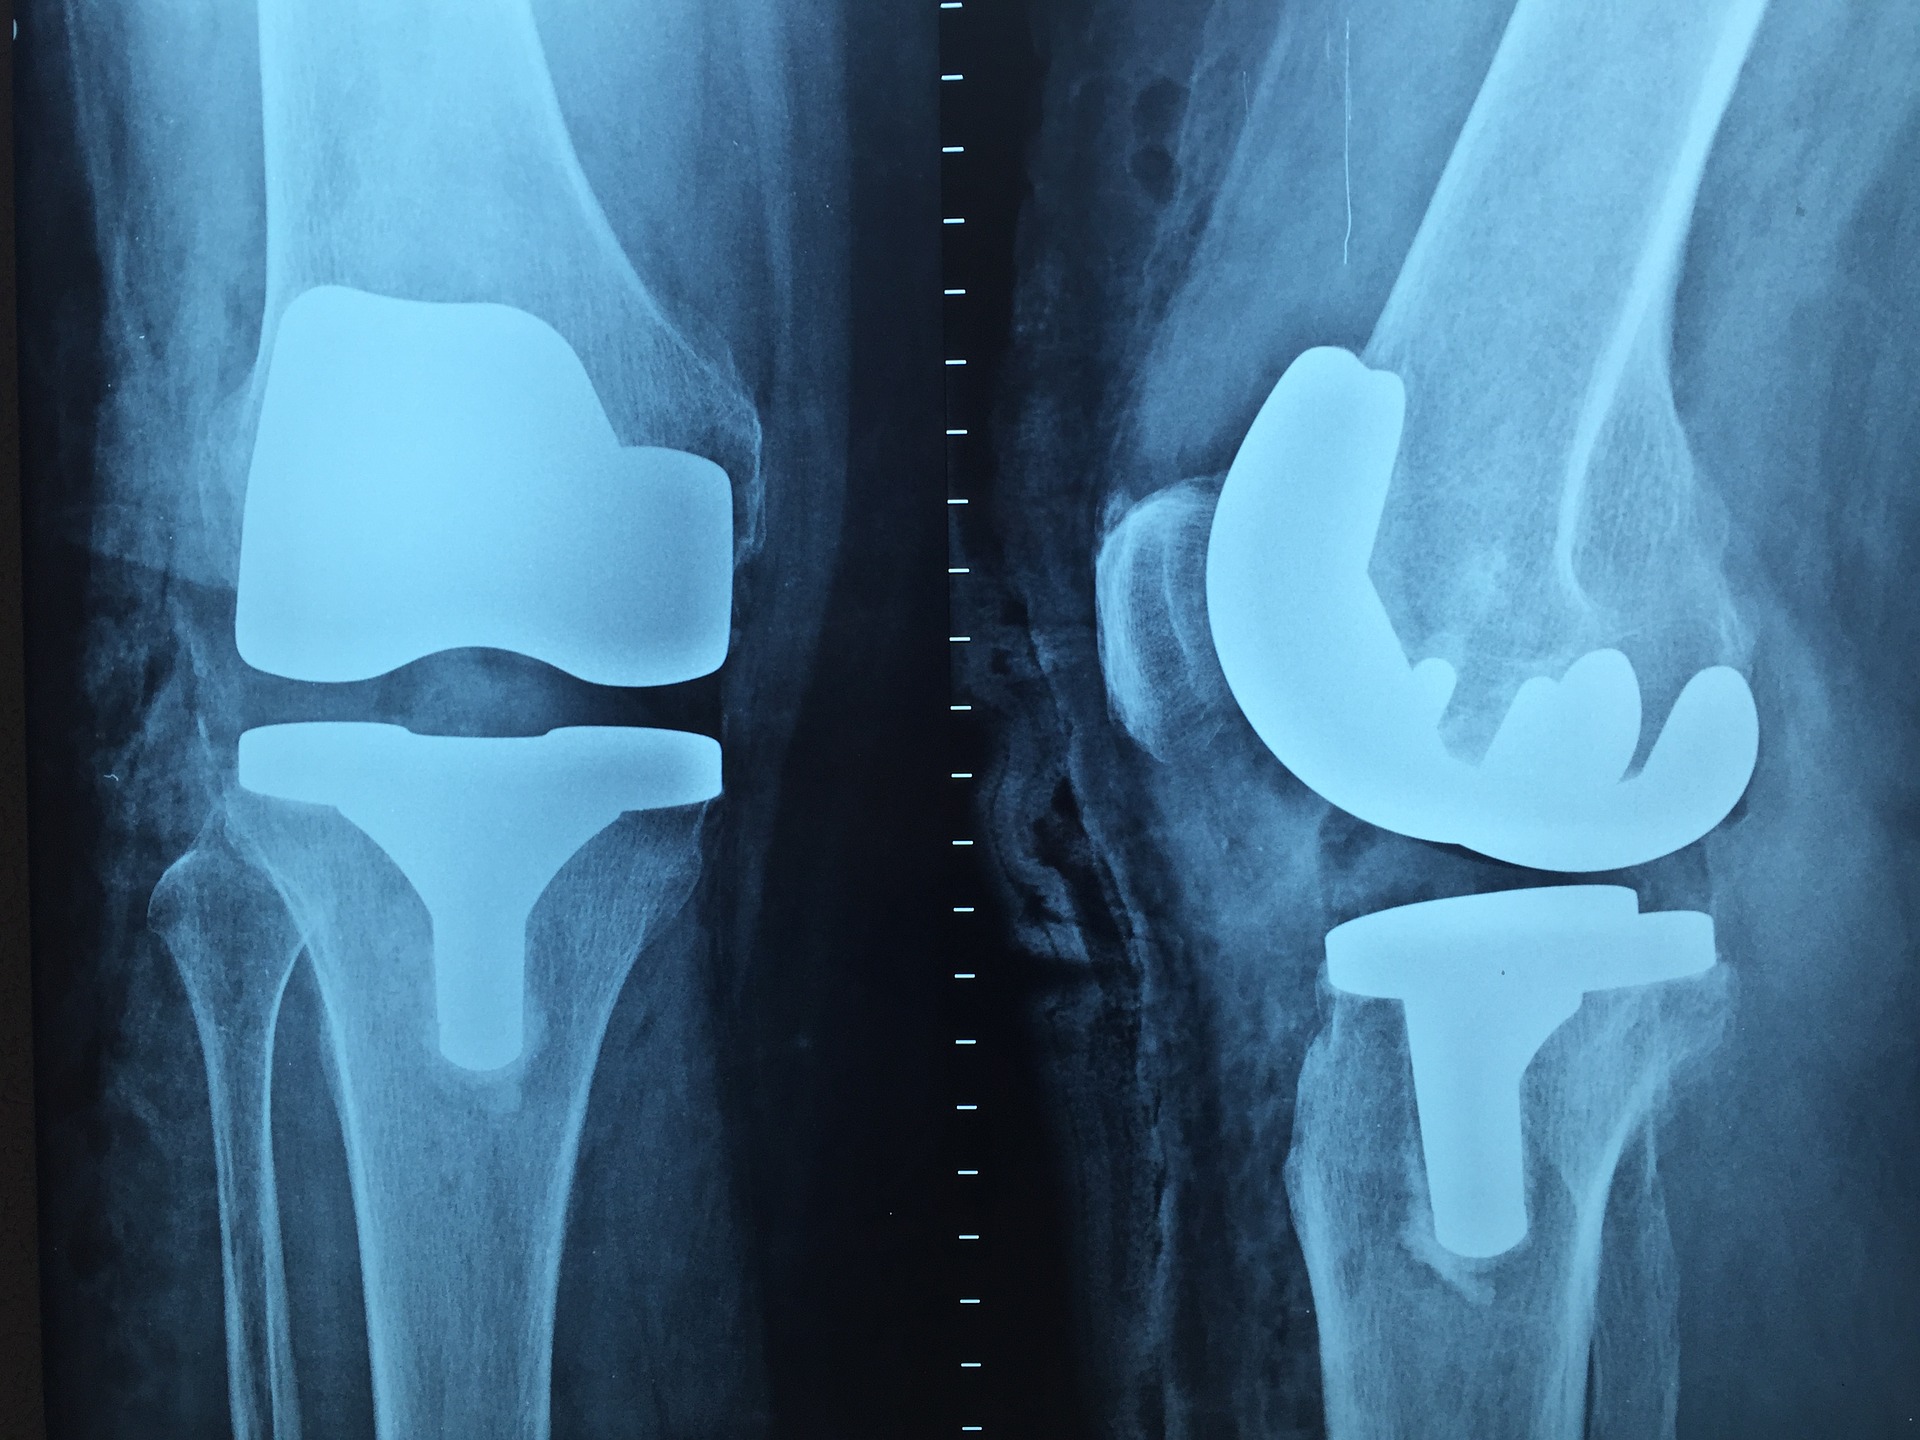

Dzisiaj coraz więcej spotyka nas różnych uszkodzeń ciała. Bardzo intensywny tryb życia czy aktywne uprawianie …